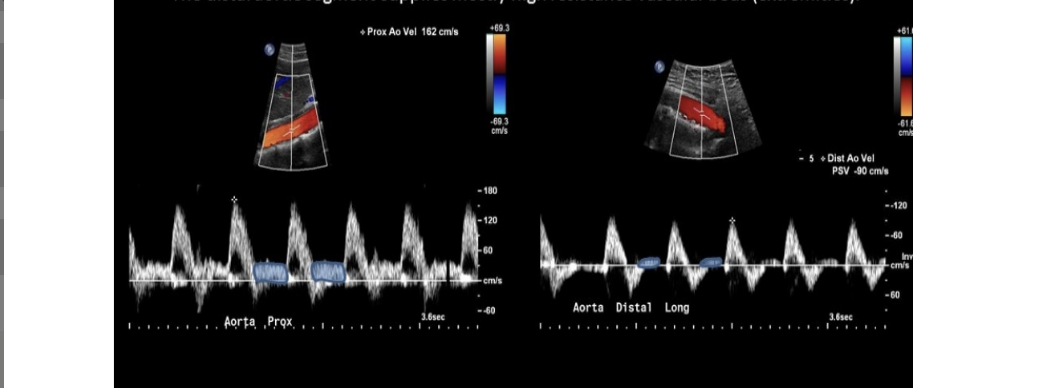

which 2 cursors would be used to measure the acceleration time for this renal artery flow

.

a) green + yellow

b) green + red

c) red + blue

d) blue + green

b. green + red